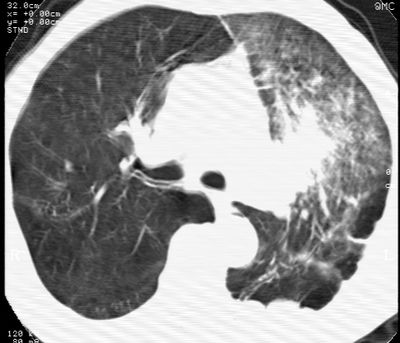

标题: CT24000:M65,胸痛,胸闷月余,既往慢支,肺气肿,肺心病 [打印本页]

标题: CT24000:M65,胸痛,胸闷月余,既往慢支,肺气肿,肺心病

左肺门肿块,相应支气管闭塞,左肺上叶、舌叶大片及散在高密度影,部分呈不张改变,两肺纹粗乱,左侧胸腔积液。考虑左侧中央型肺癌伴阻塞性改变。

左肺门见巨大软组织肿块影,直径约--,境界清,左上肺叶支气管变窄,左上肺舌叶见大片状密实影,余肺纹理增多、紊乱、纤细、部分网格状,两肺透亮度增高,纵隔内见增大多发淋巴结影,心影略左偏,左侧少量胸腔积液。

左侧中央型肺癌伴左上肺舌叶不张、纵隔淋巴结转移,左侧少量胸腔积液。